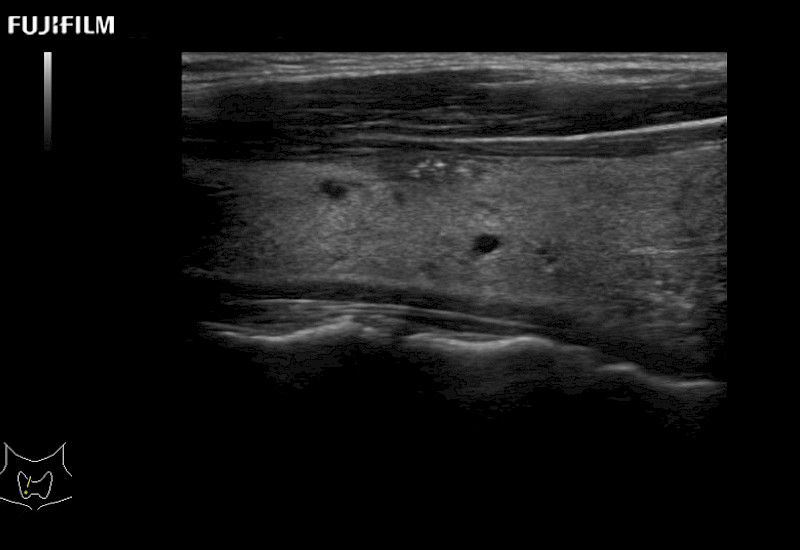

Extraordinary high-resolution digital imaging

- Exceptional near and far-field resolution

- Instant feedback on tumor margin delineation

- Valuable information to guide tumor resections

- Exceptional near and far-field resolution

- Instant feedback on tumor margin delineation

- Exceptional near and far-field resolution

- Instant feedback on tumor margin delineation